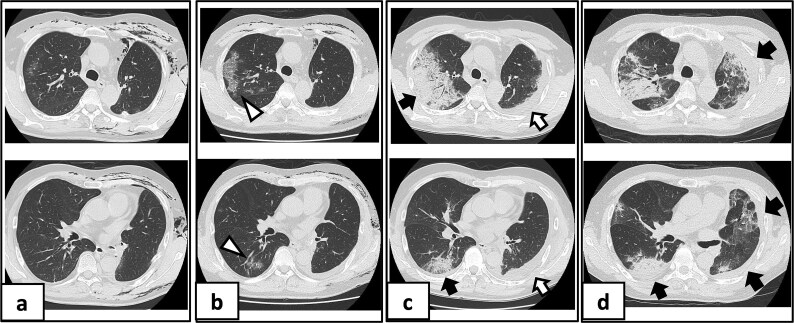

迟发性组织性肺炎作为急性冠状病毒病2019 (COVID-19)综合征的表现在围手术期尚未见文献记载。这里,一位61岁的男性接受了左下肺叶切除术,并伴有持续的漏气,需要进行7次胸膜切除术。患者于术后第10天感染COVID-19,最初恢复,但于第27天再次入院,出现发烧和呼吸衰竭。胸部计算机断层扫描显示进行性实变伴磨玻璃影。最初的甲基强的松龙脉冲治疗反应有限,需要第二个疗程加环孢素a。患者在术后第104天获得了明显的放射学改善。根据两期临床病程、独特的影像学进展和有限的类固醇反应,诊断为急性后COVID-19综合征继发迟发性肺炎。该病例强调了对肺切除术后COVID-19患者进行延长监测的重要性,以便及早发现并及时干预延迟性肺部并发症。

Delayed-onset organizing pneumonia as a manifestation of post-acute coronavirus disease 2019 (COVID-19) syndrome has not been documented in the perioperative setting. Here, a 61-year-old man underwent left lower lobectomy complicated by persistent air leakage requiring seven pleurodesis procedures. He developed COVID-19 on postoperative Day 10 and initially recovered but was readmitted on Day 27 with fever and respiratory failure. Chest computed tomography revealed progressive consolidations with ground-glass opacities. Initial methylprednisolone pulse therapy showed limited response, necessitating a second course with cyclosporine A addition. The patient achieved substantial radiological improvement by postoperative Day 104. Based on the biphasic clinical course, distinctive radiological progression, and limited steroid response, delayed-onset organizing pneumonia secondary to post-acute COVID-19 syndrome was diagnosed. This case highlights the importance of extended monitoring in post-lung resection patients with COVID-19 to enable early recognition and prompt intervention of delayed pulmonary complications.